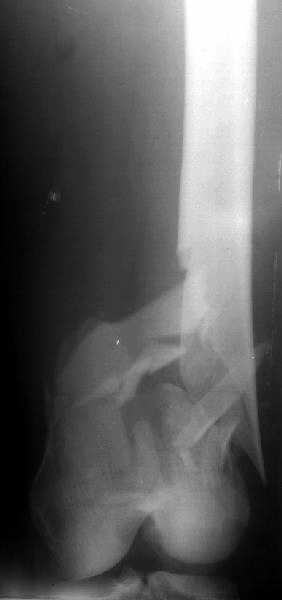

Отправитель: V. M. Iyer 01 Январь 2004, 15:17

1

The mobilisation of knee is started immediately from the second day. Weight bearing is permitted as in any other interlocked nailing. That is, Toe touch to start with and within four days, partial to in another two weeks, full weight bearing. Of course that is assuming that the correct size nail has been used. Up to 70 kg body weight, 11no will be good enough and 12mm if more.Usually at the 1st followup, at 6 weeks time, they have full flexion..I

have seen a few surgeons putting in a drain, but I have not found it unnecessary. There has never been any effusion needing active treatment.

Enclosing a recent intraop picture